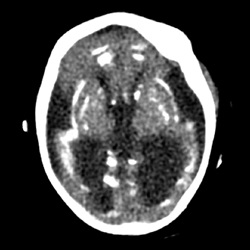

#AJNRcc >> July 22, 2024 >> What is the diagnosis for this 29-year-old pregnant woman with a 2-month history of hyperemesis gravidarum with sudden confusion, vision blurring, and altered consciousness over past 5 days? Submit your answer at https://t.co/604tEQiFye.